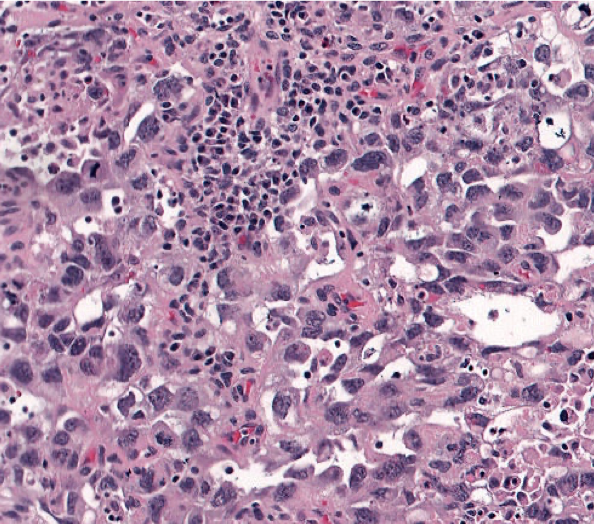

Embyronal Carcinoma

Embryonal Carcinoma